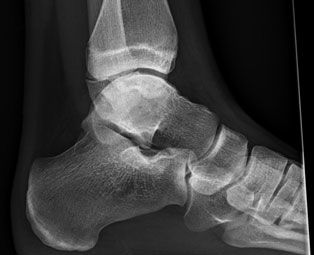

6. What do they look l   ike on X-ray?

Talar Body

Talar Body_1

Talar Body_2